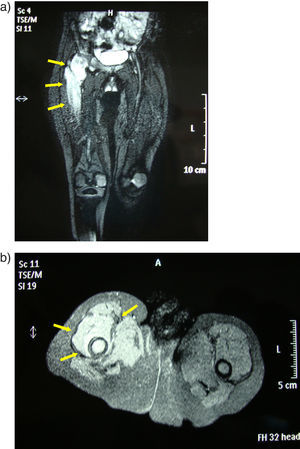

Paciente de 2 años de edad, de origen rumano, sin antecedentes de interés, que consultó por cojera de miembro inferior derecho de 3 meses de evolución. La niña estaba afebril y en la inspección se observó rechazo a la deambulación y al apoyo de dicha extremidad. En la exploración se apreció limitación y dolor a la rotación externa y abducción de la cadera. En la radiografía simple se observó desestructuración de la cabeza femoral (fig. 1). Ante la sospecha de osteomielitis se solicitó una resonancia magnética que mostró hallazgos compatibles con artritis séptica coxofemoral con osteomielitis proximal del fémur (fig. 2a y b).